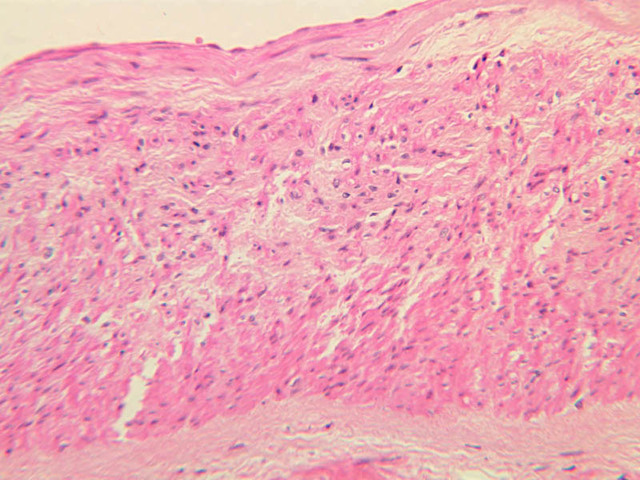

Blood passes from the elastic arteries via arteries of intermediate type into the muscular (distribution) arteries. Locate and examine a muscular artery in slide A-28 (Renal artery & vein, H&E [2.5x, 10x-labeled, 20x, 40x-labeled] [10x-labeled, 20x, 40x]; AF [10x-labeled, 20x, 40x]). Note that the tunica intima is separated from the tunica media by a thick internal elastic membrane which has a scalloped appearance. The tunica media consists of many layers of smooth muscle cells arranged concentrically in a spiral fashion (A-28, H&E [2.5x, 10x-labeled, 20x, 40x] [2.5x, 10x, 20x, 40x, 40x] [2.5x, 10x, 20x]). An external elastic membrane is present, but is thinner and less complete than the internal elastic membrane. The tunica adventitia is about equal in size to the media in this vessel and is more intensely eosinophilic in its staining properties. Note the appearance of small blood vessels in the outer part of the tunica adventitia. You may also be able to see occasional nerve fibers.